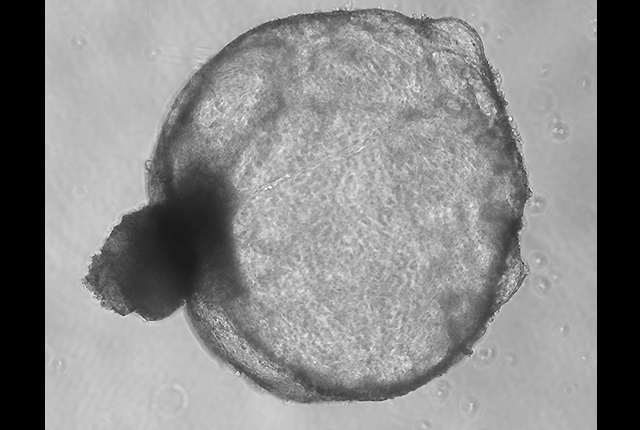

Investigator’s tiny kidney systems gain a national stage

Organoids that model human responses to potential therapeutics will join a consortium focused on polycystic kidney disease.